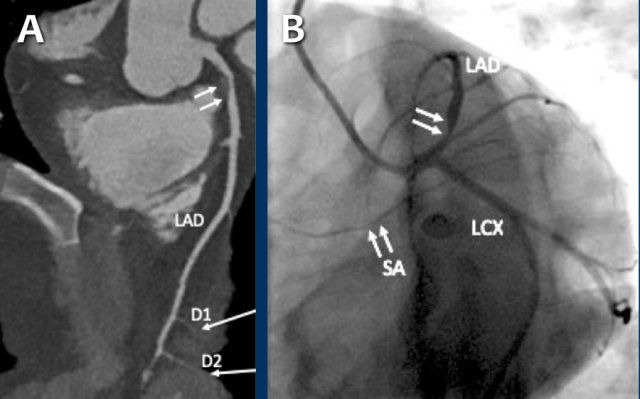

- The total calcium score of 0 indicates the absence of calcified plaque in the coronary tree.

- Severe stenosis (70-99%) in the mid LAD and D2 branch.

Continue with the next images of the same patient...

Same patient. First, study the CTA image.

How would you describe the findings?

The coronal image shows a central low-attenuation area around the lumen

of the LAD.

This low-attenuation area is surrounded by a higher attenuation

area.

This finding is the earlier discussed napkin-ring sign, which is a high-risk

plaque feature.

This patient classifies as CAD-RADS 4A/P1/HRP.

Same patient.

Double-oblique (A) and volume-rendered (B) images of the LAD showing the

location and the length of the plaque.

Also, the stenosis in the D2 branch of the LAD can be appreciated on the volume

rendered reconstruction.

Due to the degree of stenosis and the presence of napkin-ring sign (visible on

axial images) this patient underwent ICA where the presence of severe stenosis

was confirmed.

Continue with the next images...

A: ICA correlates with CTA and shows an 80% stenosis in the mid LAD (white arrows) and a 60% stenosis in the D2 branch (black arrows). The D2 stenosis was overestimated on CTA.

B: PCI was performed during which a drug eluting stent (DES) was implanted with good results (white arrows).